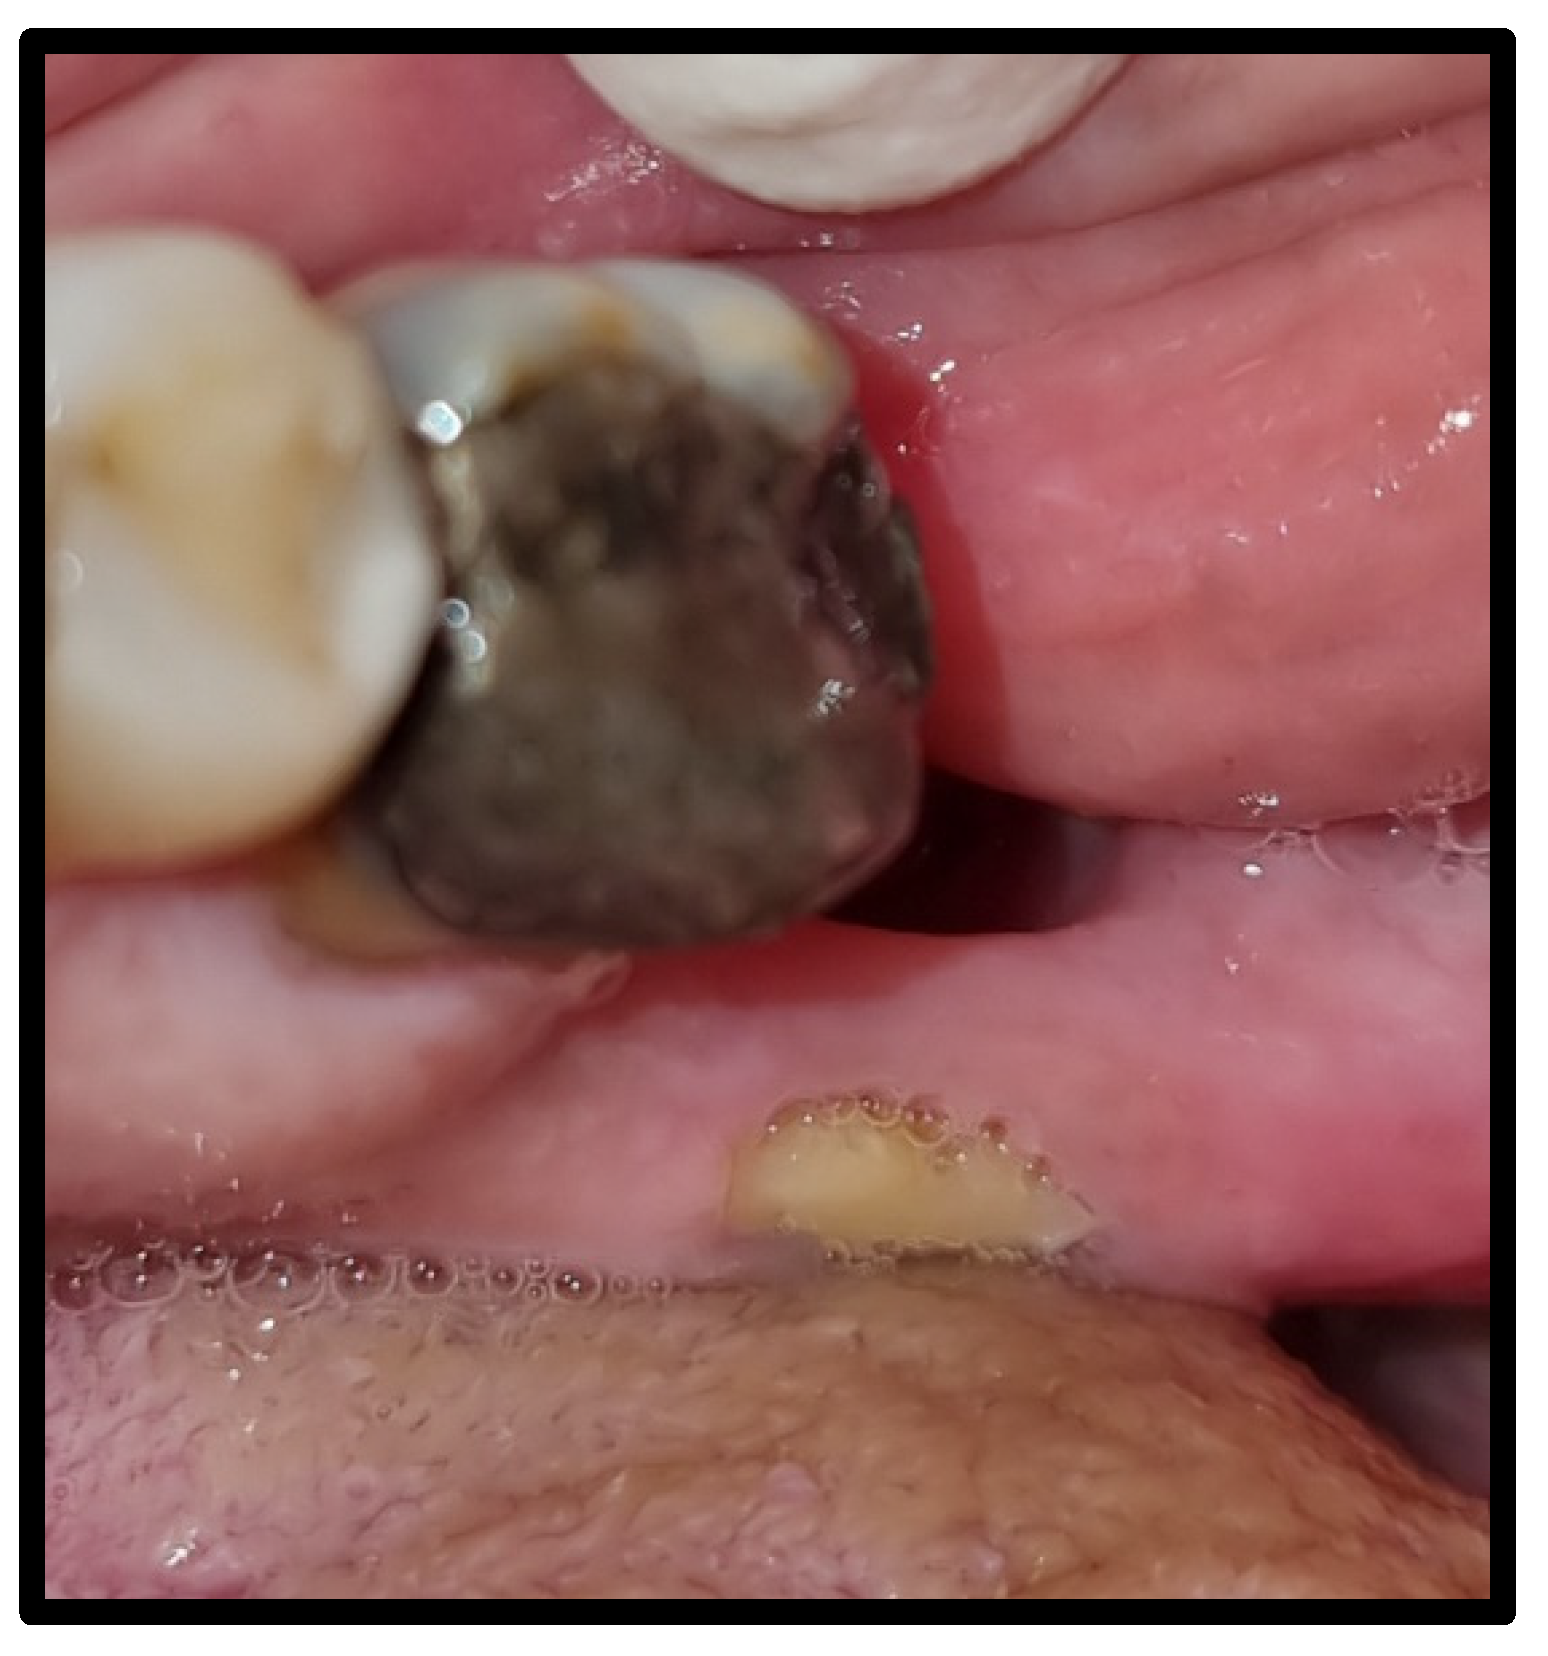

| OLP/lichenoid reaction (3 were exacerbations of previous autoimmune disease) | 12 | 50.00 | |

| Osteonecrosis of the mandible, exposed type | 6 | 25.00 | |